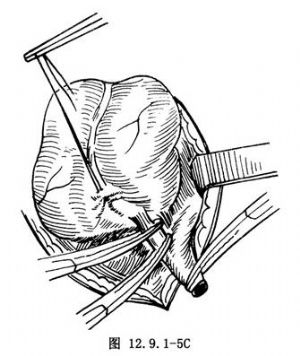

12.12 12.逆行切除法

用於盲腸後位闌尾或闌尾尖端開始不能顯露時,可按前述方法先結紮切斷闌尾根部(圖12.9.1-5A),殘株包埋後(圖12.9.1-5B),血管鉗夾持闌尾遠斷端,逐次切斷結紮闌尾系膜直至切除闌尾(圖12.9.1-5C)。